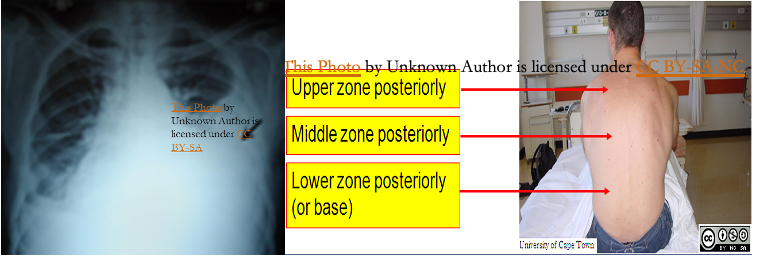

- Physical exam findings: Clinically detected if > 500 ml.

- Inspection and palpation (affected side):

- Asymmetric expansion (↓Chest movement)

- Mediastinal displacement (Trachea shifted away from the side of the lesion in massive effusion).

- Reduced tactile fremitus.

- Percussion: Stony dullness

- Auscultation:

- Faint or absent breath sounds over the area of effusion

- Vocal resonance - reduced or absent

Chest X-ray: Lateral decubitus view (most sensitive): > 200 ml.

- Unilateral blunting of the costophrenic angle

- Homogeneous density with a meniscus-shaped margin (meniscus sign)

- Complete opacification of the lung (Large effusion) and Mediastinal shift and tracheal deviation.